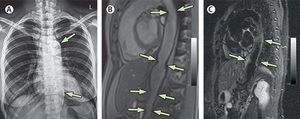

A 40-year-old woman presented with complaints of a 4-year history of recurrent central chest pain. She gave a history of having a prolonged fever for about 3 months accompanied by arthralgia at the age of 13 years, but the fever resolved gradually. What is the diagnosis? A) Hyperparathyroidism B) Idiopathic hypercalcaemia C) Aortic aortitis D) Hyperlipidaemia

C. Did the fever and arthralgia at age 13 contribute or cause the aortitis?